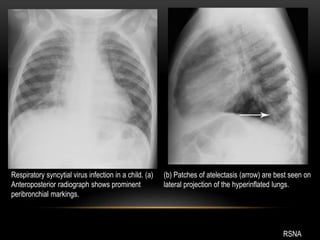

Respiratory syncytial virus infection in a child. (a)

Anteroposterior radiograph shows prominent

peribronchial markings.

(b) Patches of atelectasis (arrow) are best seen on

lateral projection of the hyperinflated lungs.

RSNA